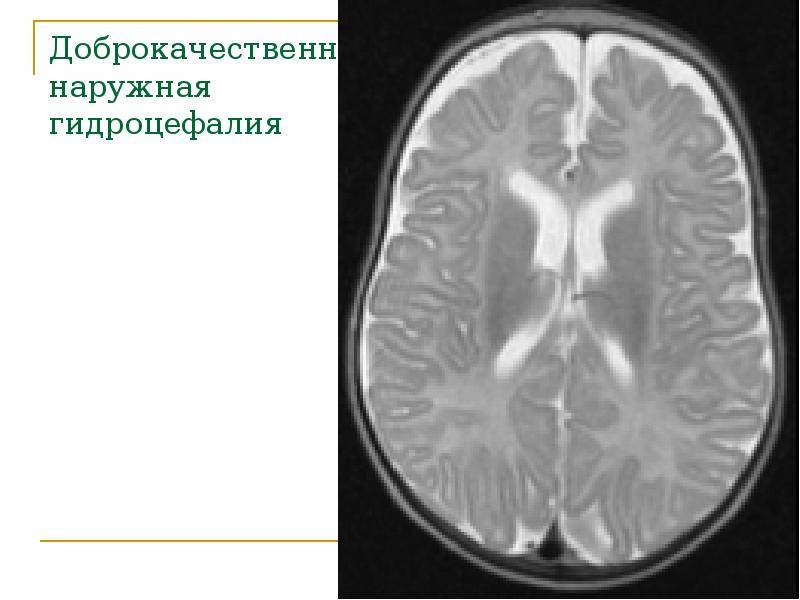

Признаки умеренно выраженной наружная

Признаки умеренно выраженной наружная 113 фото